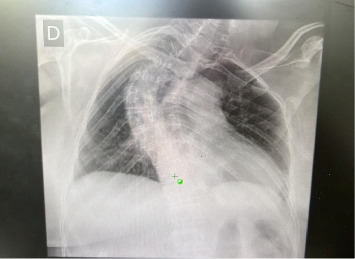

56岁女性患者,无明显合并症,乳房检查结果异常。影像学示左乳一5.4 cm不规则结节,诊断为浸润性乳腺癌(NST, 2级)。新辅助化疗开始,导致病变大小减少。手术干预包括象限切除术、前哨淋巴结活检和腋窝淋巴结切除术,发现残留癌和阳性淋巴结。术后观察到乳糜通过Portovac引流管排出,提示再次手术,在此过程中发现损伤的淋巴管。中链甘油三酯保守治疗导致引流逐渐减少。患者术后第13天出院,接受辅助放疗,目前门诊定期随访。

A 56-year-old female patient, with no significant comorbidities, presented with abnormal breast exam findings. Imaging revealed a 5.4-cm irregular nodule in the left breast, diagnosed as invasive breast carcinoma (NST, Grade 2). Neoadjuvant chemotherapy was initiated, leading to a reduction in lesion size. Surgical intervention included quadrantectomy, sentinel lymph node biopsy, and axillary lymphadenectomy, which revealed residual carcinoma and positive lymph nodes. Postoperatively, chylous drainage through a Portovac drain was observed, prompting reoperation, during which the injured lymphatic duct was identified. Conservative management with medium-chain triglycerides resulted in a progressive reduction of drainage. The patient was discharged on the 13th postoperative day, subsequently underwent adjuvant radiotherapy, and is currently receiving regular outpatient follow-up.